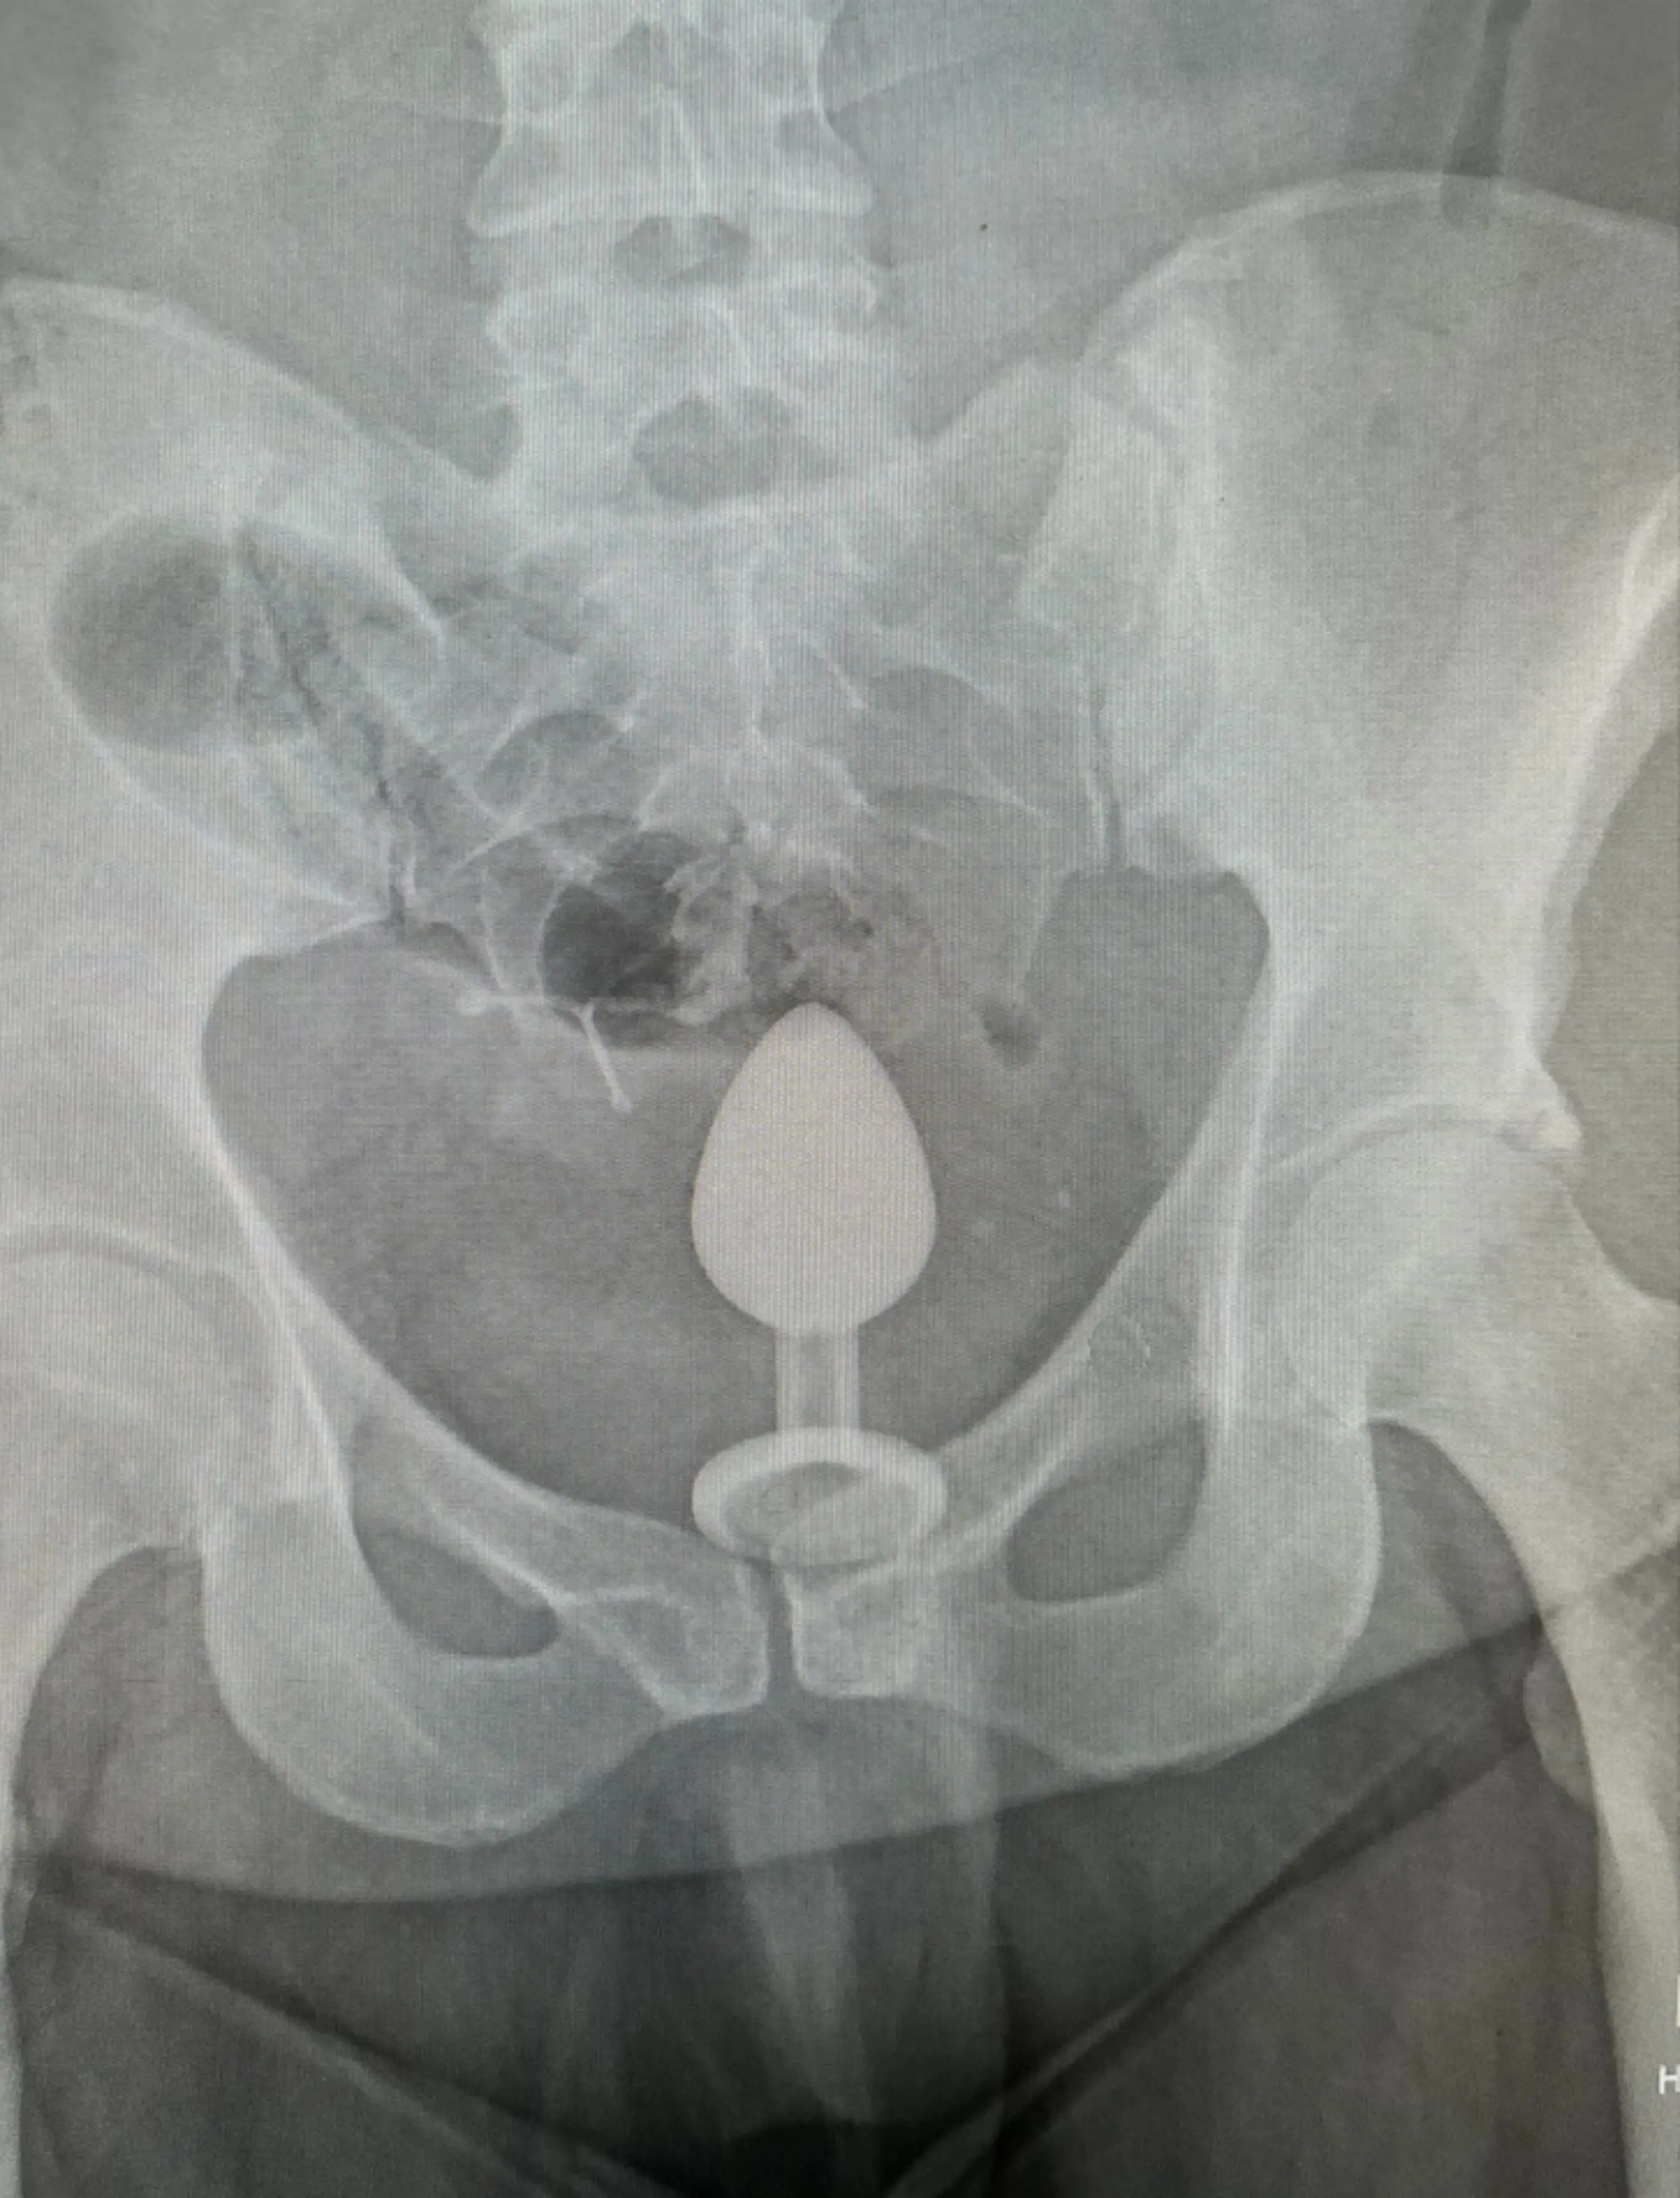

A woman was left ‘mortified’ after being rushed to A&E with an adult toy stuck inside of her - revealing the X-ray to prove it.

Gigi Chapman, 34, who is originally from Northampton, says she was having ‘fun’ with a ‘friend with benefits’ when the pair decided to use a three-inch metal sex toy she purchased online. Check out how it happened:

She initially thought that her friend put the anal toy in too deep and assumed he had taken it out when the discomfort subsided - but soon learned that her body had actually ‘sucked’ the adult toy up.

The content creator, who now lives in Manchester, shared the 'awkward' incident on TikTok, explaining that the toy got lodged so far up her bottom that she needed medical intervention.

Gigi says the toy was removed by hand in an 'excruciating' procedure at A&E that she compared to how she imagines childbirth to feel.